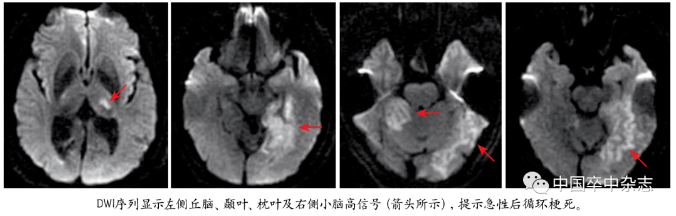

首次发病当日急诊CT检查显示左侧丘脑、颞叶、枕叶及右侧小脑新鲜脑梗死(图1);第二次复发当日的CT检查显示右侧小脑出现新的梗死灶(图2);第三次复发的第二天进行了CT检查,结果显示左侧小脑可见新鲜的梗死灶(图3)。